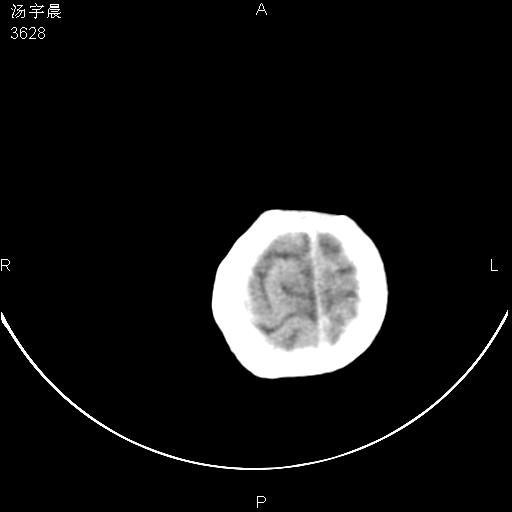

早产儿,现两月大,2月份在某医院诊断病毒性脑炎并治疗,mri报右颞部脑白质片状长t2信号,脑白质模糊。其他不详,现家属要求ct复查 。

双侧大脑半球大片状低密度,无明显占位表现, 符合病毒性脑炎。

小儿病毒性脑炎ct表现缺乏特异性,但其定位分布有一定特异性,单纯疱疹病毒性脑炎ct表现以颢叶病变为主,同时可累及其他脑区或伴出血,乙型脑炎表现为基底及丘脑的病变,流行性腮腺病毒性脑炎则ct表现可正常,故ct检查对病毒性脑炎的定性有重要的价值。 本例支持:病毒性脑炎的后遗改变!